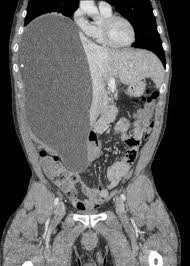

Final Diagnosis Right Subphrenic Intraperitonal Encapsulated Csf Csf Pseudocyst Collection Containing The Distal Ventriculoperitoneal Catheter Abdominal Cysts